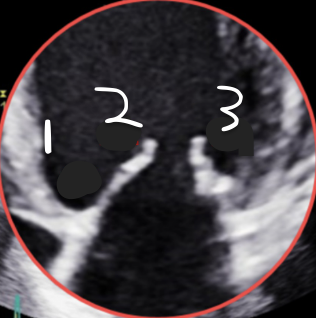

This is 4CH, What is 1?

A3

This is 4CH, What is 2?

A2

This is 4CH, What is 3?

P1